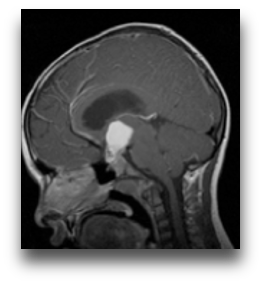

下面这个案例来自鲁特卡教授曾接诊过的一位9岁患儿。她因头痛及视野受限被诊断出一个巨大囊性颅咽管瘤,在经过VP分流术并植入Ommaya储液囊后,肿瘤体积明显缩小,在MRI上几乎看不到。